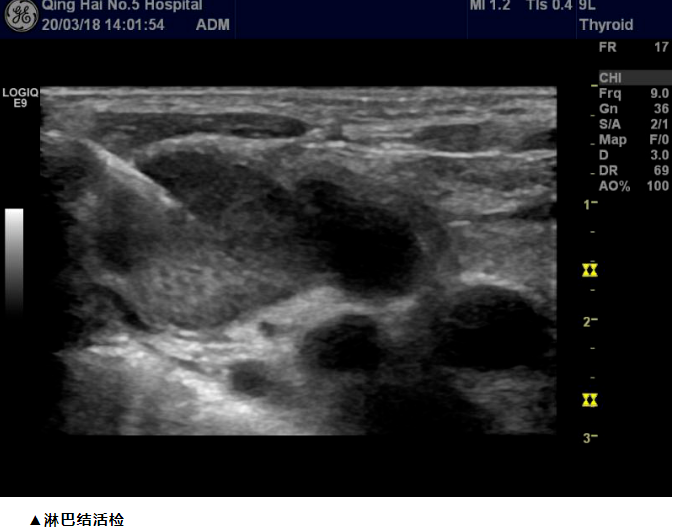

小小穿刺针有如此独特的优势和威力,精准微创治疗为危重病人带来了康复希望。那么什么是超声介入呢,让我们来认识一下吧:  超声介入也叫“介入超声”,它是现代超声医学的一个分支,是在超声显像基础上为进一步满足临床诊断和治疗需要而发展起来的一门新技术。其主要特点是在实时超声的监视或引导下,完成各种穿刺活检、引流、冲洗、注药治疗等操作,可以避免某些传统外科手术,达到与外科手术相媲美的效果,超声介入的核心是用最小的代价达到最佳的诊疗效果。  1、精准安全、实时监视,穿刺针直达病灶区域,进行诊断或治疗操作;  2、痛苦小、操作时间短,无辐射,微创,治疗过程疼痛小; ◆超声引导下甲状腺细针穿刺活检(FNA)、乳腺、淋巴结、肝、肾等肿物穿刺活检术。

◆超声引导下腹腔(肝、胰、双肾、肾上腺、胃肠道、腹膜后、直肠)等深部病变组织的穿刺组织学活检;胸部外周(胸壁、胸膜、肺外周型占位活检)等组织学活检。